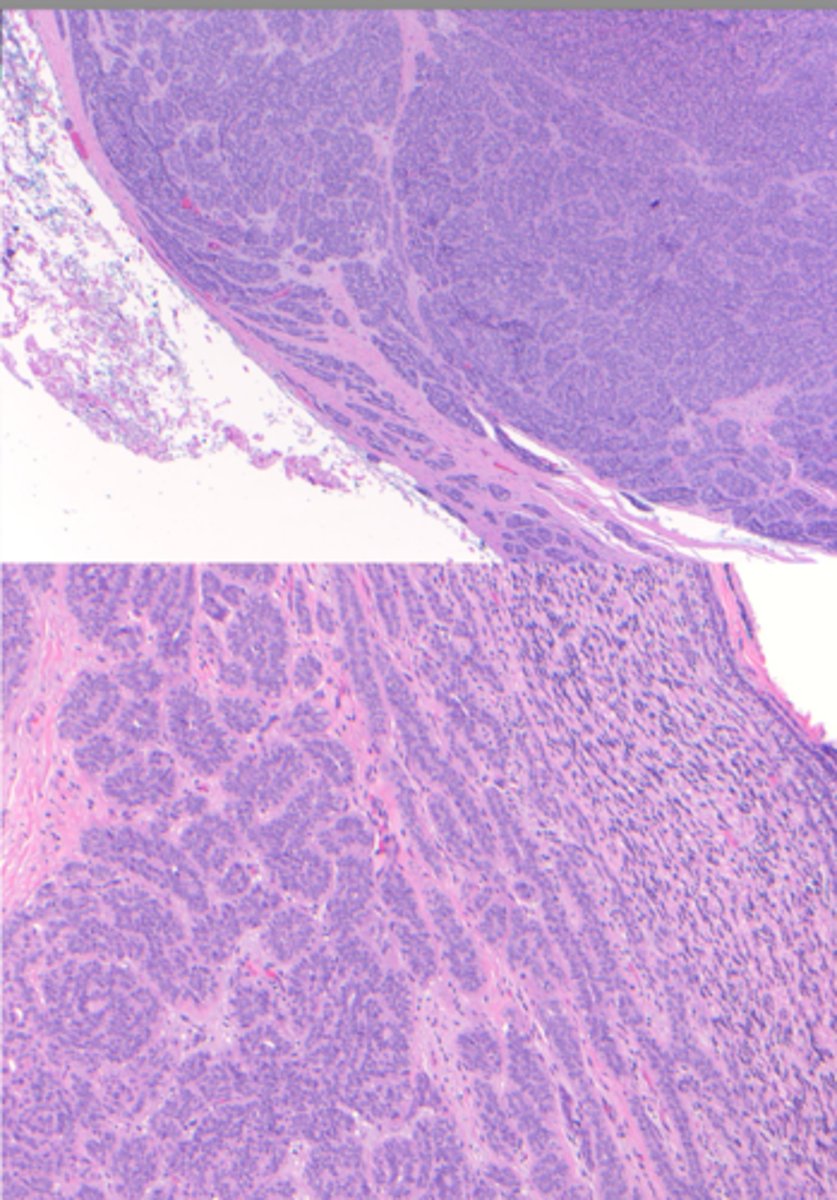

Carcinoma Ex PA

Malignant Salivary Gland Tumors:

-Malignant transformation of a PA(pleomorphic adenoma)!

-Middle aged and older

-History of a lesion present

for many years

-Rapid growth

▫ pain, ulceration

▫ facial nerve palsy

-Most in parotid

-Minor SG→ most on

palate

A: benign

B: Malignant